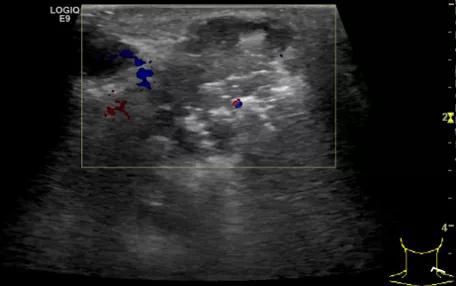

随后,徐栋教授进一步分享了五个临床实战病例,带来了更直观的热消融治疗经验。第一个病例是62岁肺癌患者,术后1年余发现双侧锁骨上淋巴结复发,侵犯神经,存在静脉回流、淋巴回流障碍,肿胀、疼痛非常明显。影像显示患者淋巴结边界不清、形态不规则,存在浸润,血流强化增强。由于患者在系统治疗后进展,且主要目的缓解症状、减瘤。局麻下行热消融术,从后向前逐层消融,热消融之后超声造影即刻评估显示完全充盈缺损,完全覆盖病灶。

(病例1图例)

第二例是食管癌患者,术后半年余锁骨上固定淋巴结可触及肿大,疼痛非常明显,系统治疗后无缓解,患者希望通过局部处理缓解症状。造影显示强化信号明显,结节部分区域坏死,故主要针对强化区域从后向前的逐层的消融,皮下进行液体隔离减少烫伤。热消融后影像显示血流增强消失,弹性、硬度增高,一个月后复查显示充盈缺损,完全消融,疗效远超预期。

(病例2图例)